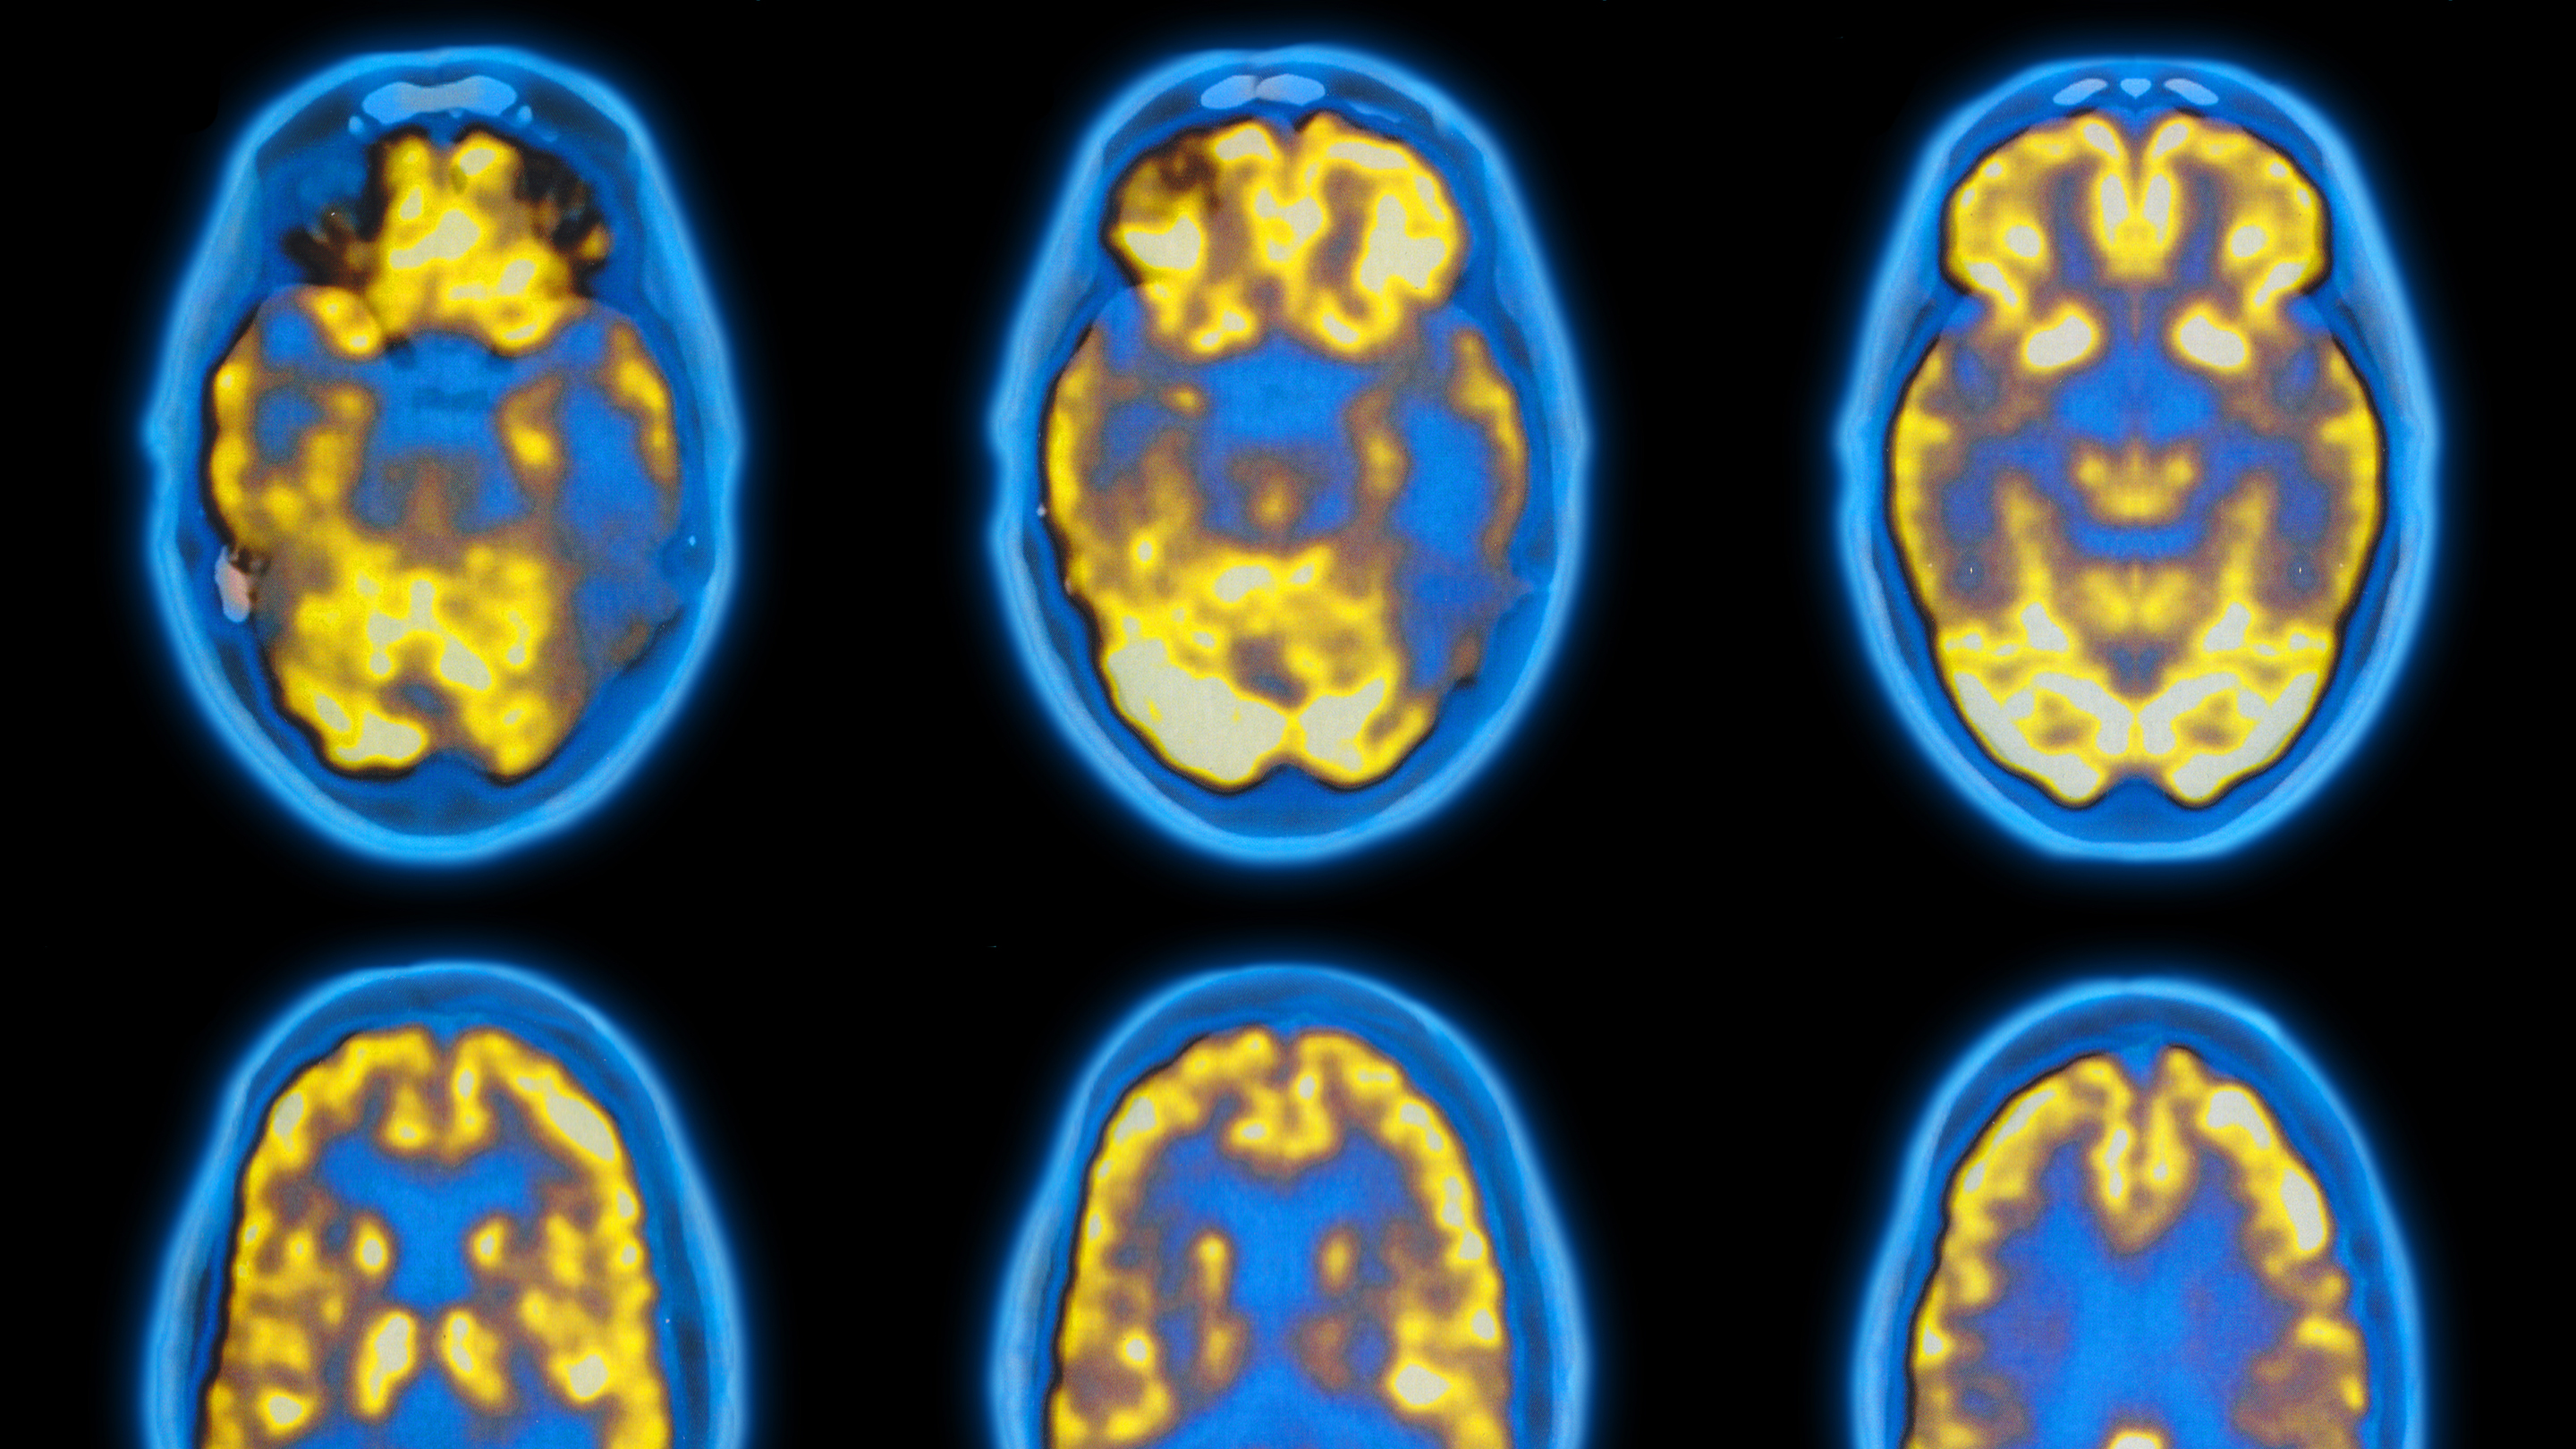

PET scan of a brain